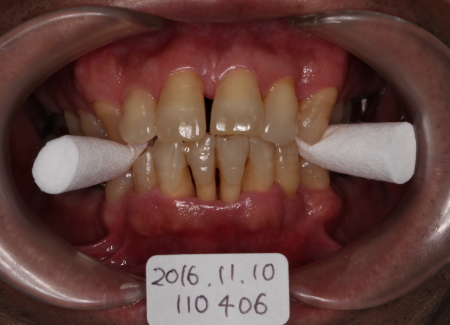

主訴:歯牙の動揺

FOP

縫合

2016-11-11

FOPの翌日

痛みもほとんどなく歯ぐきの状態も良好